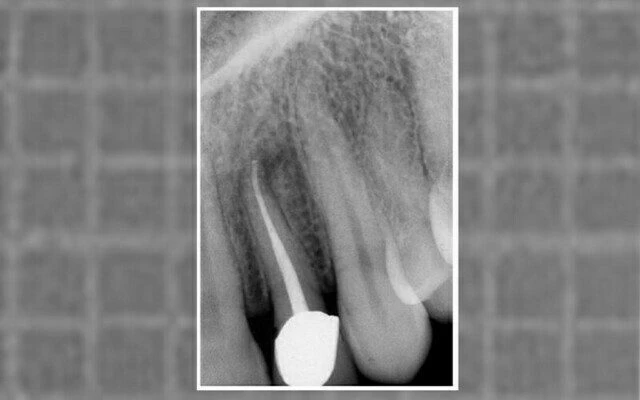

phim sau điều trị

Hình 11.39. Phim sau điều trị của 1 răng cửa bên trên với 1 đoạn cong về phía xa ở 1/3 chóp.